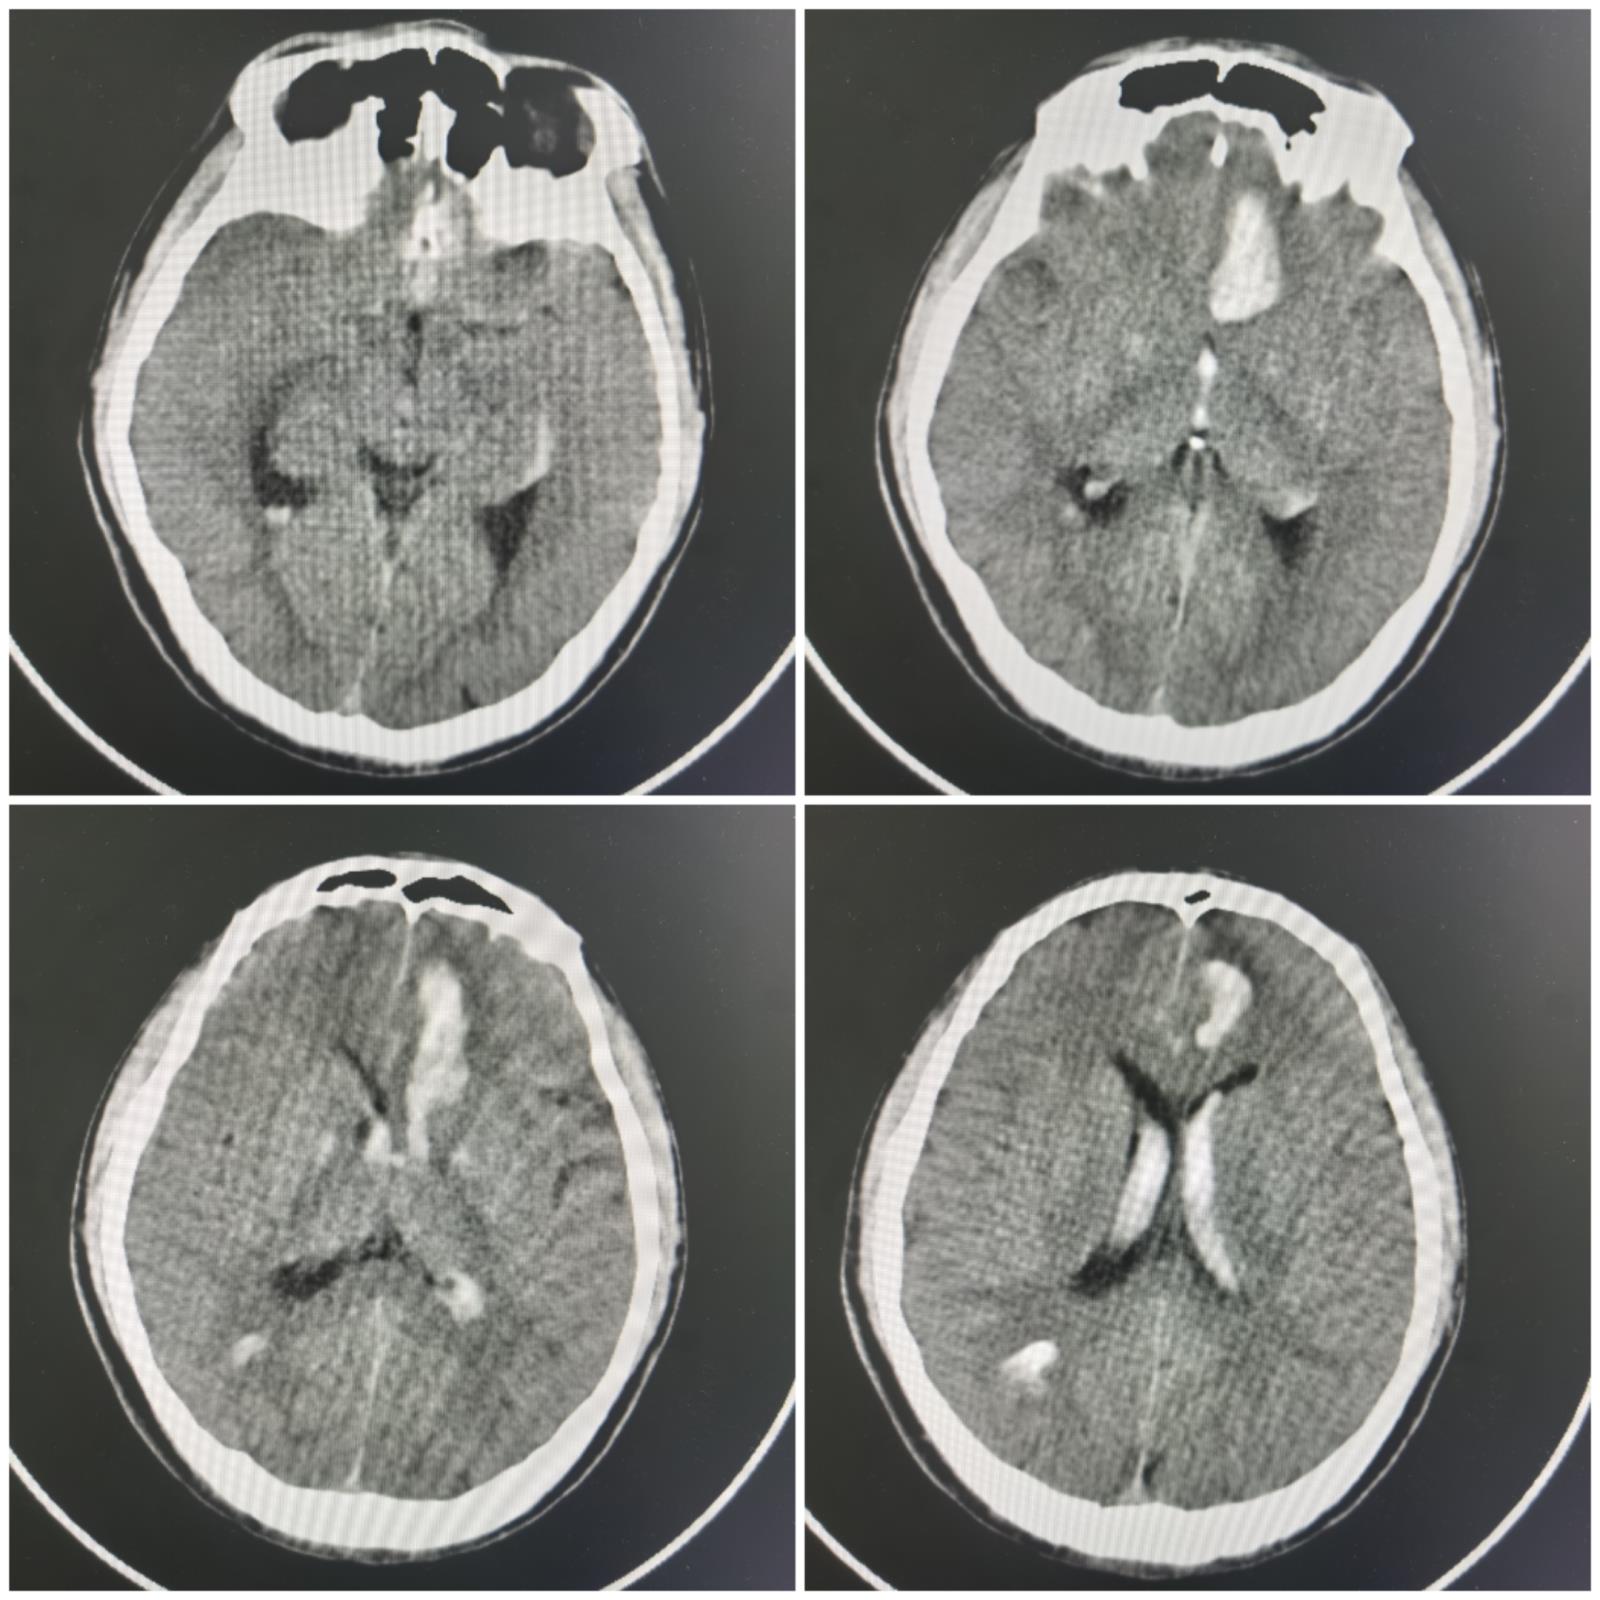

术前影像